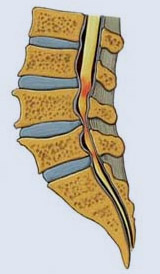

La estenosis raquídea O RAQUIESTENOSIIS ES EL ESTRECHAMOENTO DEL CONDUCTO DE LA COLUMNA QUE ES POR DONDE PASAN LOS NERVIOS QUE NO DAN LA MOTRICIDAD Y SENSIBILIDAD DE LAS EXTREMODADES: “.

Por lo tanto, la estenosis espinal es un estrechamiento de la columna. Para explicarlo más en detalle, la estenosis espinal se da cuando se estrechan los canales por los que viajan la médula espinal y las raíces nerviosas, y se hacen tan estrechos que la médula y las raíces se comprimen PROVOCANDO DOLOR EN EL CUELLO PERDIDA DE LA SENSIBILIDAD Y FUERZAS EN LOS BRAZOS O LAS PERNASQUE PUEDEN LLEGAR HASTA UNA PARALISIS EN LOS CASOS SEVEROS

“Nervios y médula espinales comprimidas. Puede conducir a dolor en la parte baja de la espalda, las piernas, el cuello, los brazos o las manos. Todo depende de en qué parte de la espalda se están comprimiendo la médula espinal y/o los nerviosa puede ser a nivel cervical y lumbar

La estenosis espinal puede producirse en cualquier lugar de la columna, pero es más probable en la parte inferior de la espalda (región lumbar) o en el cuello (columna cervical). Tiene sentido que si la estenosis se produce en la parte baja de su espalda se la llame estenosis espinal lumbar y si es en el cuello, estenosis espinal cervical.